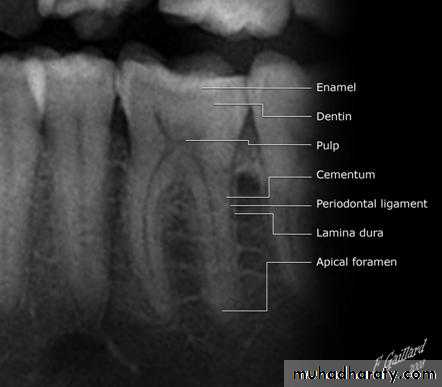

Normal Apical TissuesIn this category the patient is asymptomatic and the tooth responds normally to percussion and palpation testing. The radiograph reveals an intact lamina dura and periodontal ligament space around all the root apices.

Periradicular tissues consist of cementum, periodontal ligament, and alveolar boneCementum is a mineralized, avascular connective tissue and consists of three different types. Many growth factors, such as insulin-like growth factor-1 (IGF-1), fibroblast growth factors (FGFs), epidermal growth factor (EGF), bone morphogenetic proteins (BMPs), transforming growth factor- β (TGF- β ), and platelet-derived growth factor (PDGF), are contained in the cementum matrix released under certain conditions and associated with cementoblast proliferation, migration, and differentiation during cementum wound healing

The periodontal ligament is a soft, specialized connective tissue that connects the cementum to the alveolar bone. Periodontal ligament contains heterogeneous cell populations and extracellular matrix (ECM). The cells of the periodontal ligament include osteoblasts, osteoclasts, fibroblasts, epithelial cell rests of Malassez, macrophages, cementoblasts, and undifferentiated mesenchymal cells (stem cells). The ECM of the periodontal ligament consists of collagen fibers, fibronectin, elastin, other noncollagenous proteins, and proteoglycans.

Alveolar bone or alveolar process is that part of bone of the jaws housing the sockets for the teeth. It consists of outer cortical plate, a central spongy or cancellous bone, and bone lining the sockets. Bone matrix contains IGFs, TGF- β , BMPs, FGF, and PDGF.